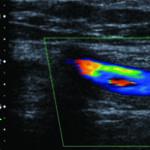

El estudio normal implica un flujo laminar, en sincronía con los latidos cardíacos, el examen de color homogéneo y un análisis espectral trifásico, con velocidades adecuadas de acuerdo al nivel arterial examinado (Fig. 13).

La Ultrasonografía y el examen con DC resultan el método no invasivo de elección para el diagnóstico de enfermedades vasculares. Permite determinar las características del vaso, el tipo, grado y localización de las estenosis con lo cual facilita la planificación del tratamiento.

El examen de las arterias de los miembros inferiores comienza por el sector ilíaco y utilizando transductores de 3 a 5 Mhz; para la evaluación de las arterias infra-inguinales empleamos transductores de mayor frecuencia (6-7-8 MHZ).